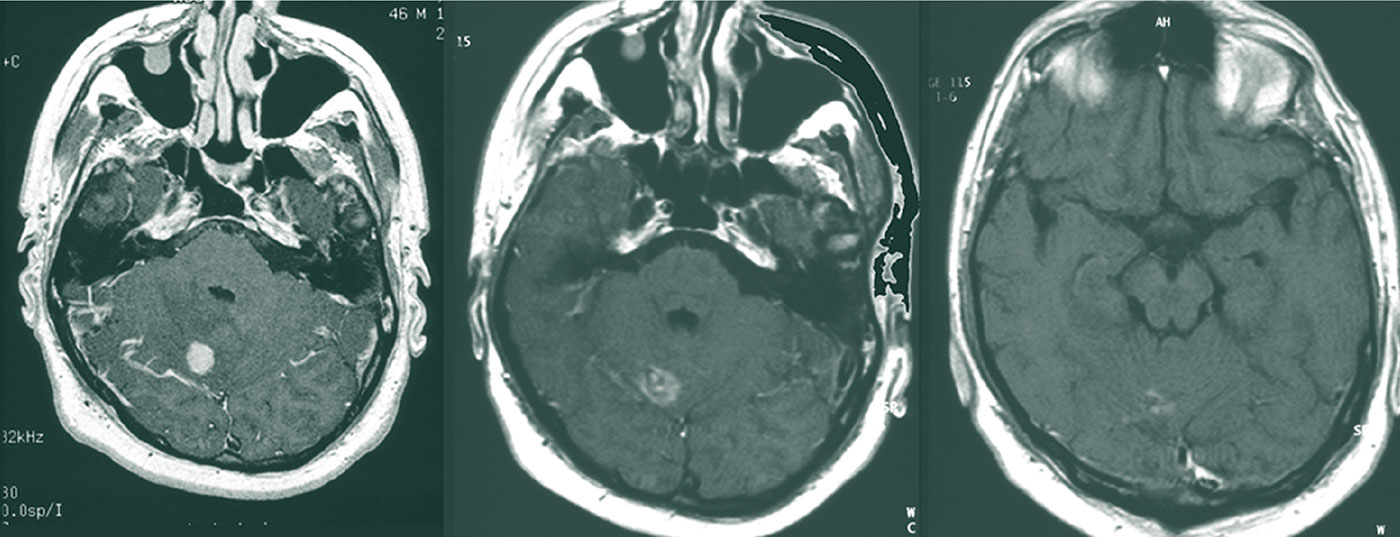

Die Inzidenz von Hirnmetastasen nimmt proportional zur verlängerten Überlebenszeit zu, wodurch die Prognose deutlich verschlechtert wird. Intensitätsmodulierte Techniken der Strahlentherapie können den Hippocampus schonen.

Die Inzidenz von Hirnmetastasen nimmt proportional zur verlängerten Überlebenszeit zu, wodurch die Prognose deutlich verschlechtert wird. Intensitätsmodulierte Techniken der Strahlentherapie können den Hippocampus schonen.